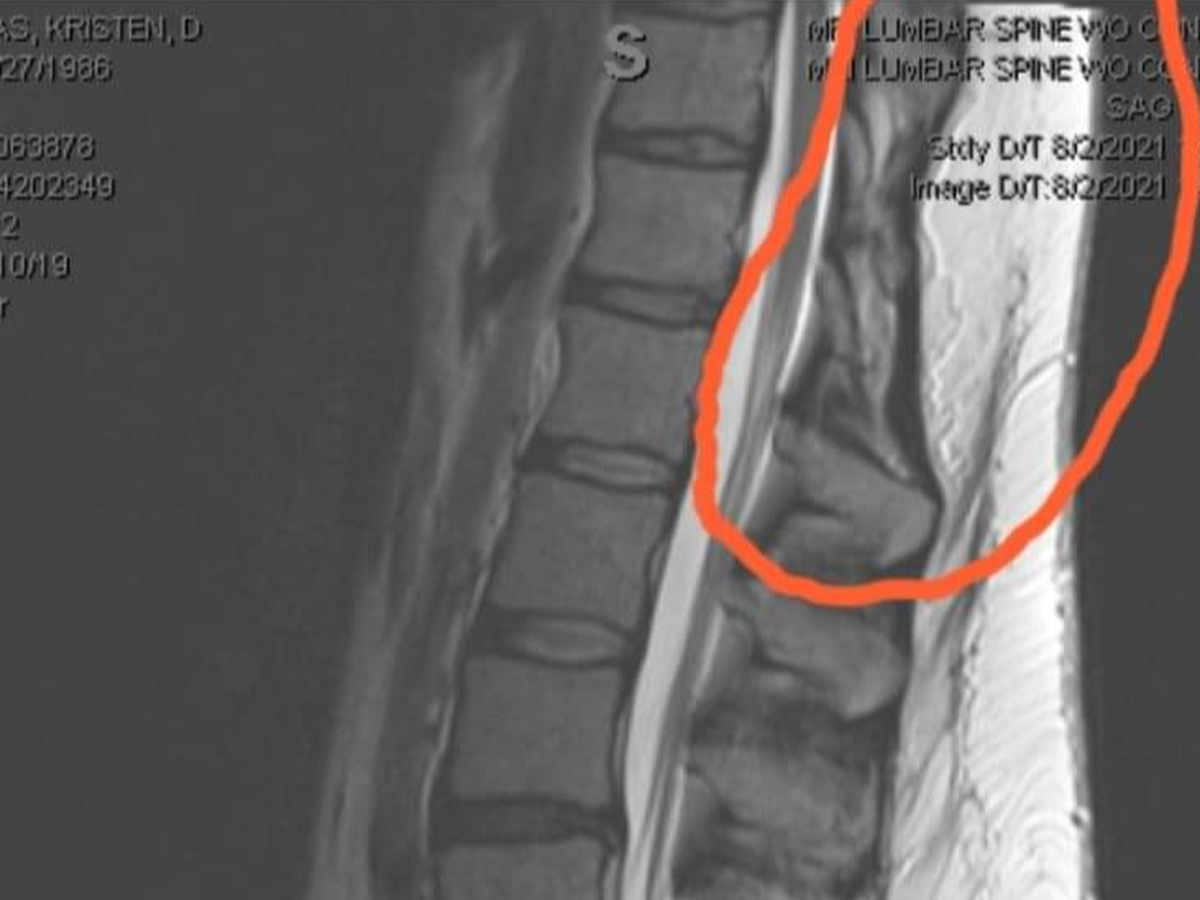

I was born with spina bifida, but I wasn’t diagnosed until a month ago! And when I tell you I had to FIGHT for anyone to even take me seriously... I'm not exaggerating. I don't think anyone else has the specific form I have... I'm missing multiple thoracic spinous processes. Over the years, my condition worsened since I didn't know I had it, leading to intense pain, mobility issues, and the need for multiple surgeries. So far, I have had 18 surgeries, including three brain surgeries and in December for major spine surgery. It included an L2-5 laminectomy, left L3-4 microdiscectomy, L4-5 transforaminal interbody fusion, L2-5 posterolateral fusion with my bone as well as deceased donor bone grafts, and fixing extremely bulging discs and veins. And I already have retrolisthesis in one of the fusions, which is another rare spinal condition. :'(

Unfortunately, my fight isn’t over. I need another surgery to untether my spinal cord, which is causing severe nerve damage and weakness. Without it, my ability to walk and function will continue to deteriorate. After that, my 20th surgery for a thyroglossal duct cyst behind my hyoid bone still needs to be removed so it cannot become cancerous in the future.